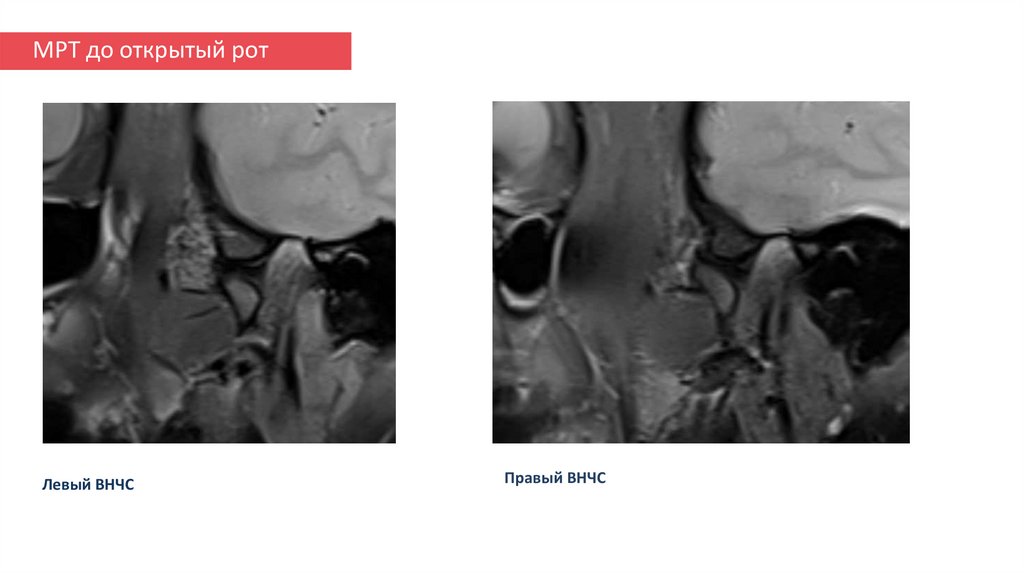

МРТ после открытый рот

18. МРТ до открытый рот

Левый ВНЧС

Правый ВНЧС